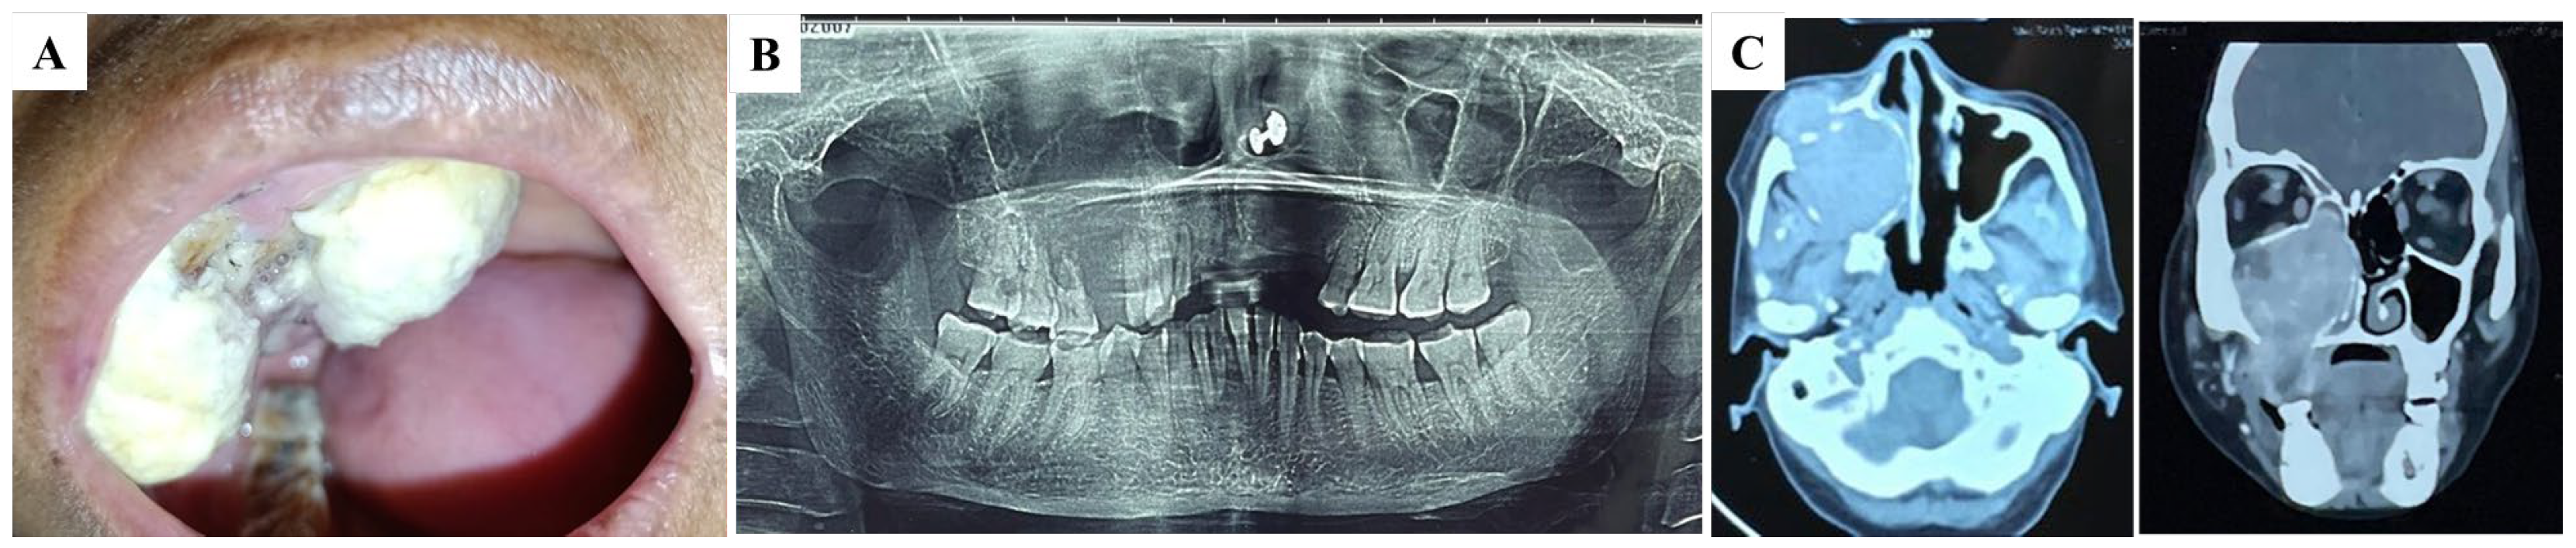

Upon performing an intraoral examination, a double-lobed nodule involving both the buccal and palatal mucosa was identified in the right maxilla (Figure 1A). The lesion measured approximately 60 mm × 50 mm × 30 mm and was covered with a white pseudomembranous surface. There were no signs of regional lymphadenopathy, and a complete head and neck examination revealed no other abnormalities. An incisional biopsy was performed to obtain tissue for histopathological analysis. The biopsy results indicated that the lesion was highly suggestive of renal clear cell carcinoma (RCC).

Figure 1.

Clinical, radiographical, and CT scans of the oral and maxillofacial region. (A) Intra-oral view of the initial lesion. A double lobe nodule is observed in the right maxilla. (B) A panoramic radiograph displays a radiolucent lesion with an indistinct margin, suggesting osteolysis between teeth 12 and 17. (C) A CT scan of the maxillofacial area shows a soft tissue lesion in the right maxillary sinus with heterogeneous enhancement and destruction of the bony wall.

Radiographic imaging was subsequently conducted to evaluate the extent of the lesion and its relationship with the surrounding structures. A panoramic radiograph revealed a radiolucent lesion with a diffuse border extending from the distal aspect of the right lateral incisor (#12) to the mesial surface of the right second molar (#17). This indicated osteolysis between teeth 12 and 17 (Figure 1B). To gain more detailed insight into the lesion and its behavior, a CT scan of the maxillofacial region was performed. The scan revealed a moderate, heterogeneous enhancing soft tissue density lesion in the right maxillary sinus with destruction of the surrounding bony wall. The lesion extended into the oral cavity, involving the right buccal mucosa and the roof of the mouth. Additionally, mucosal thickening was observed in the right frontal, sphenoid, and ethmoid sinuses, suggesting that the tumor had spread beyond the maxillary sinus and affected nearby sinuses (Figure 1C).